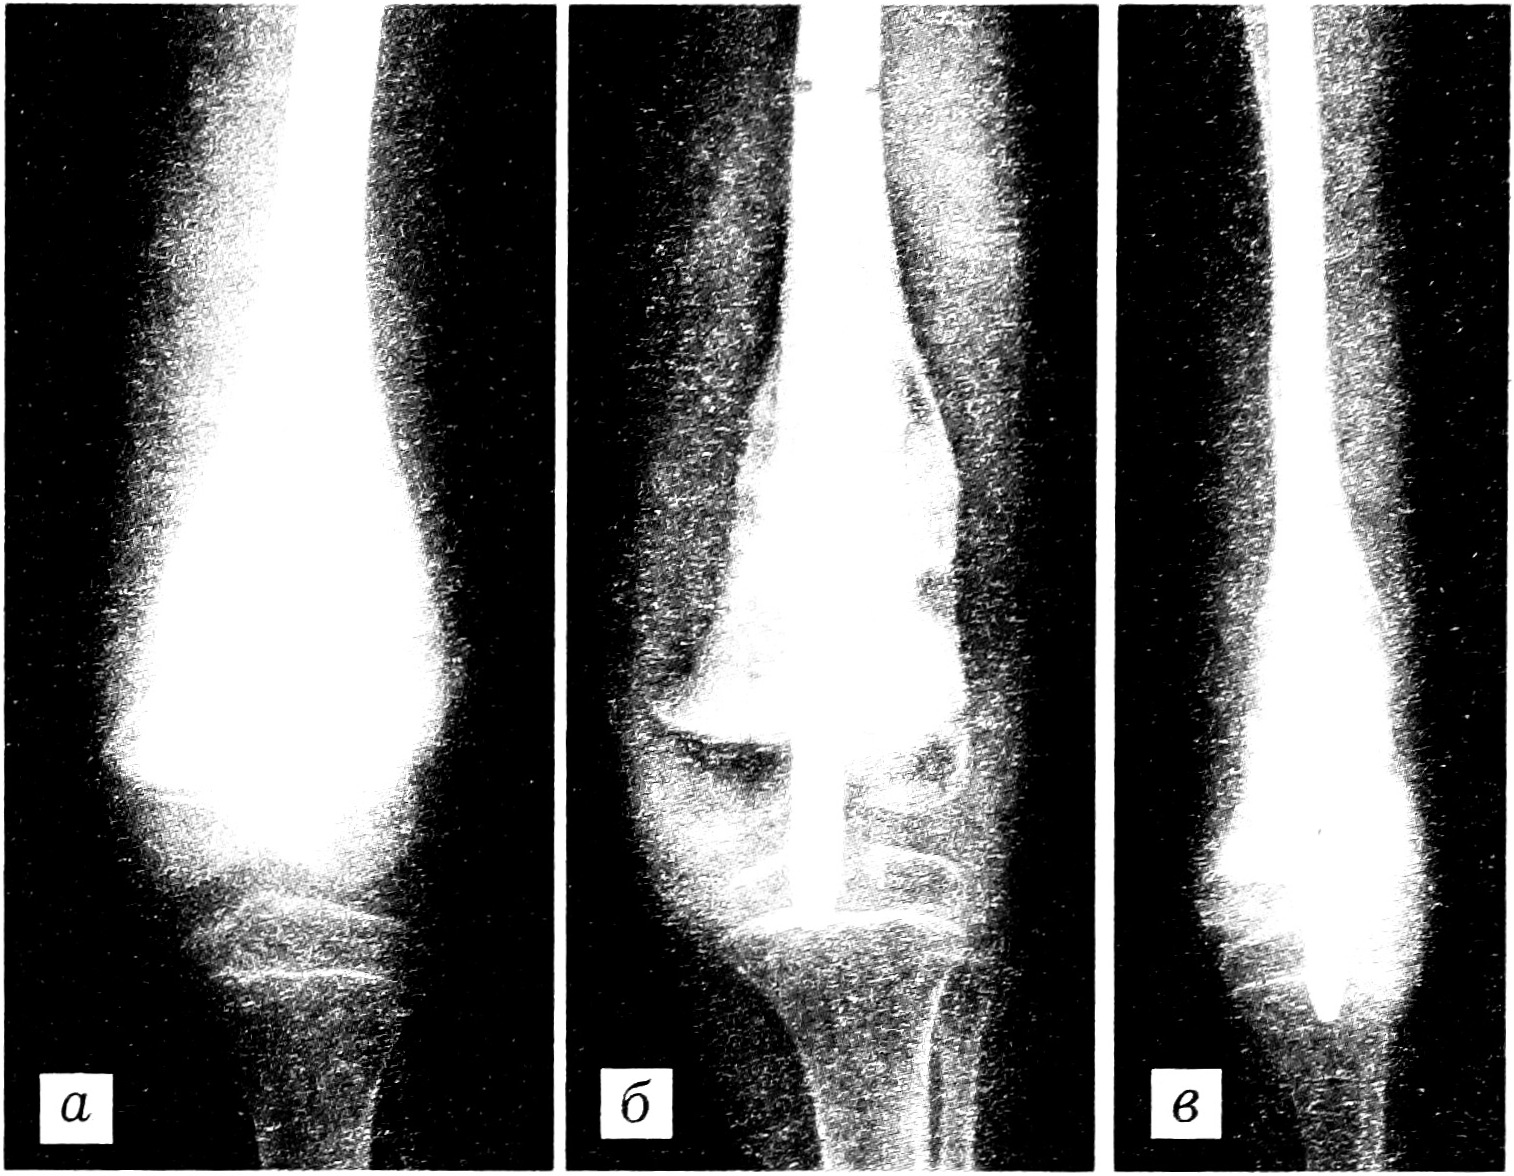

Больной В., 8 лет, поступил в радиологическое отделение МРНЦ 16.02.95. При поступлении диагностирована остеогенная саркома нижней трети левой бедренной кости (см. рисунок, а). Диагноз подтвержден данными морфологического исследования. Больному проведены облучение опухоли в СОД 36 Гр и химиотерапия цисплатином. 26.05.95, через 3 мес после лучевого и химиолечения произведена операция: резекция суставного конца бедренной кости на протяжении 17 см, однократное облучение его в дозе 60 Гр и реплантация с фиксацией металлическим штифтом (см. рисунок, б). Заживление первичным натяжением. После операции проведено 2 курса химиотерапии производными платины. Через 1,5 года после операции определяется сращение фрагментов кости, восстановление непрерывности ее кортикального слоя (см. рисунок, в). Больной остается под наблюдением.

Рис. 1. Рентгенограммы больного В. с остеогенной саркомой нижней трети левой бедренной кости.

a — при поступлении; б — после резекции суставного конца бедренной кости и пересадки предварительно облученного реплантата с фиксацией металлическим штифтом; в — через 1,5 года после операции: сращение фрагментов кости, восстановление непрерывности кортикального слоя.